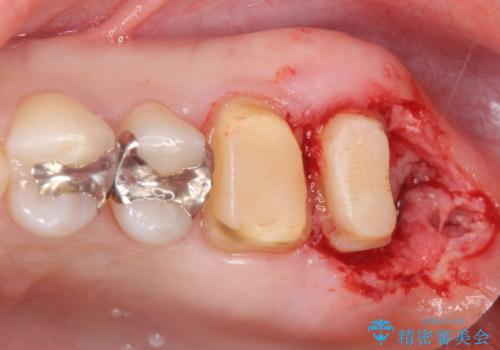

- 銀歯をやりかえたいが他院で抜歯と言われセカンドオピニオンで来院。適合の悪い被せ物が入っており、まずは古い材料、虫歯をとり保存可能か確かめる必要があり、拡大鏡下で全て取り除いたら歯質が歯茎の中まで虫歯がありました。このまま無理やり型取りをして被せ物を作っても不適合な被せ物が入る可能性が高いため歯茎を切り取る手術(ディスタルウェッジ)を行いました。そして再根管治療を行いゴールドの被せ物で治療を行いました。

- PGAクラウン・仮歯 13.2万円×2 精密根管治療(リトリートメント)・コア 16.5万円×2 ディスタルウェッジ 1万円費用は治療当時の料金となります